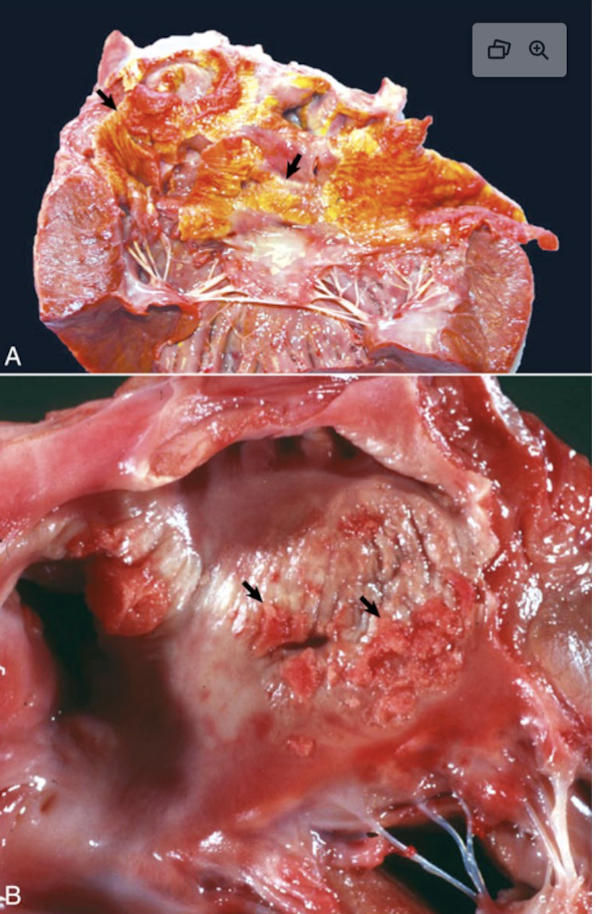

What is this showing?

vegetative valvular endocarditis